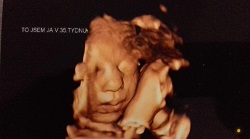

Kontrola a 3D foto

V pátek jsem byla na kontrole a fotka 3D se povedla. Další kontrola po Vánocích hnedka. Budou i natáčet ozvy miminka.